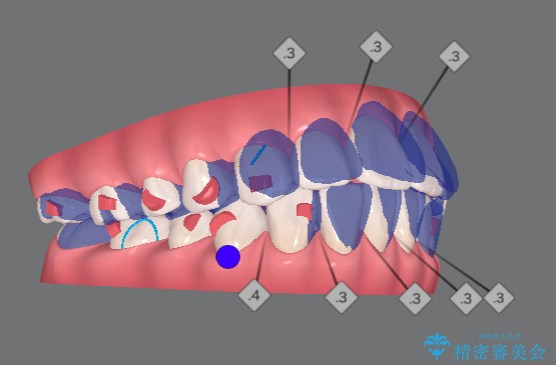

[ マウスピース矯正 ] 出っ歯に見える前歯を改善したい

・2級性の咬合関係(上顎前突) ・前歯の傾斜

を改善すべく、マイクロインプラントを用いた奥歯の後方移動を行い上記の問題を解決していきます。

マイクロインプラントを用いてしっかりと後方移動を行ったことで、奥歯の咬合関係・前歯の傾斜をしっかりと改善し、機能的・審美的に大きく改善する矯正治療を行うことができました。